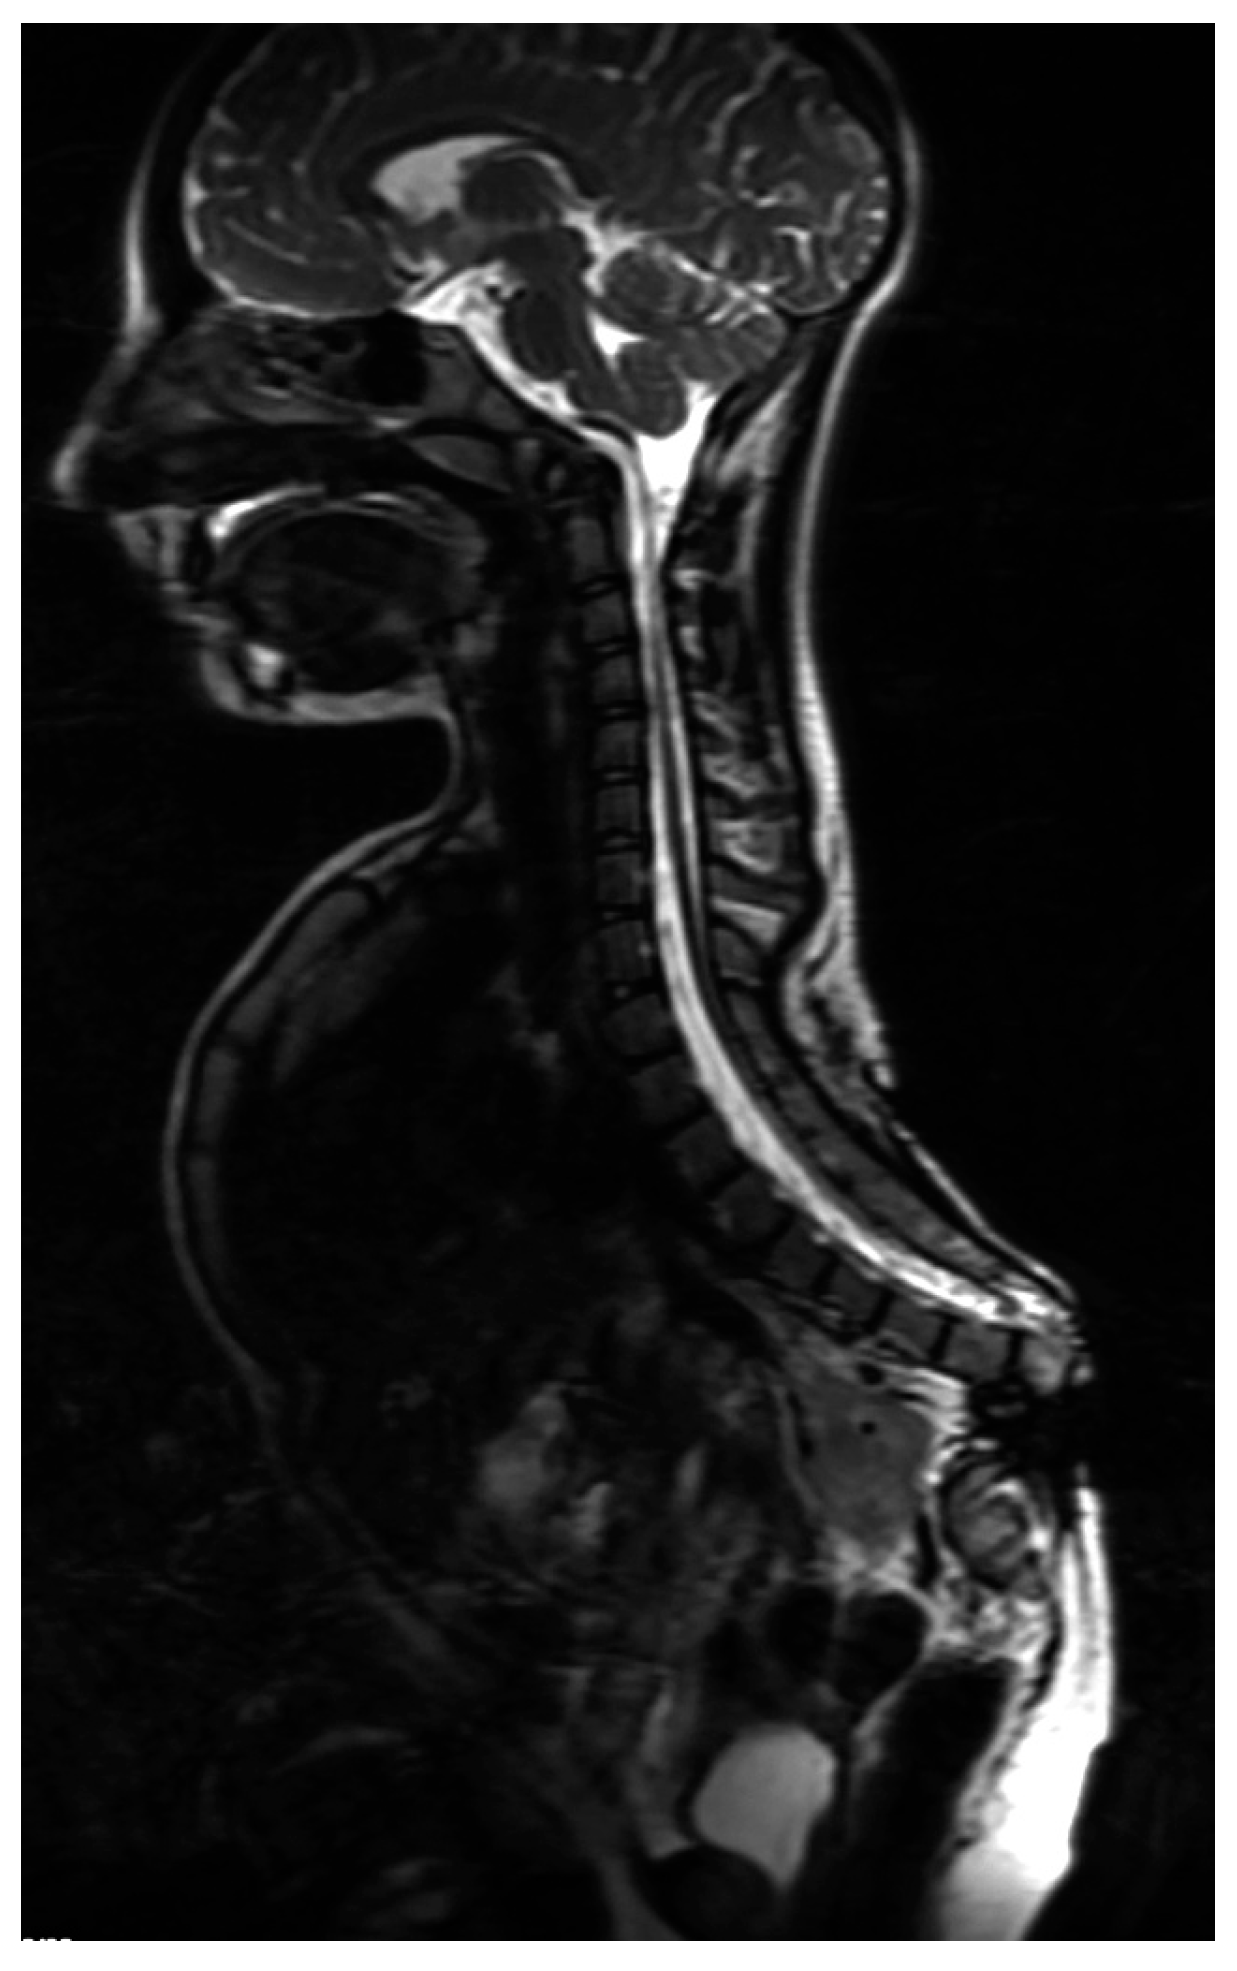

5. Morphology Symptoms

7.1. Spine

- Kapoor, S.; Pradhan, G.; Gautam, V.K.; Ratan, S.K.; Singh, A. Scoliotic deformity and asymptomatic cervical syrinx in a 9 year old with caudal regression syndrome. J. Pediatr. Neurosci. 2012, 7, 191–193. [Google Scholar] [CrossRef] [PubMed]